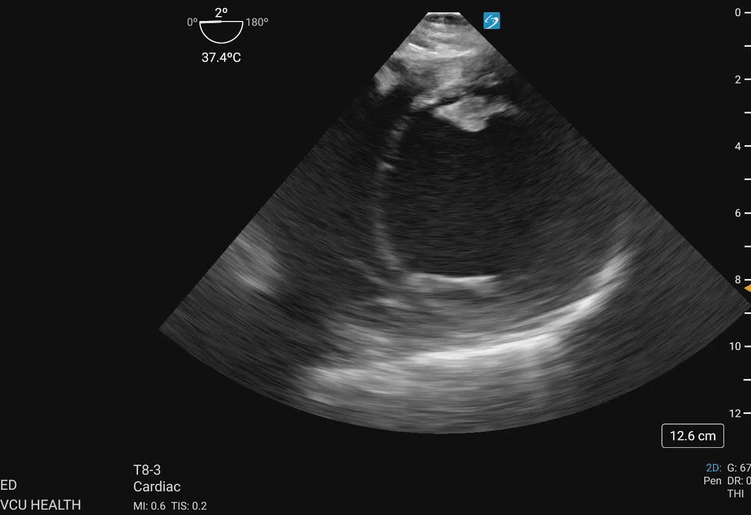

In the focused approach utilized in resuscitative TEE, evaluation of regional wall motion abnormalities in the major vascular territories of the left anterior descending (LAD), left circumflex (LCx), and right coronary artery (RCA) can be performed using the TG SAX view at the level of the midpapillary plane. To obtain this view, the operator will advance the TEE probe to an approximate depth of 40cm from the incisors, set the omniplane angle between 0-20 degrees, and anteflex the probe sufficiently to obtain the view demonstrated in Figure 1 and Figure 2. With slight adjustments in the depth of insertion further assessment of the base and apex of the left ventricle can be obtained.

Transgastric_Figure_2_compressed.gifFigure 2. Transgastric midpapillary view demonstrating the left ventricle and papillary muscles visualized at approximately 40cm depth from the incisions, omniplane between 0-20 degrees, and anteflexion of the probe. This patient demonstrates global left ventricular hypokinesis. Image courtesy of Lindsay Taylor, MD.